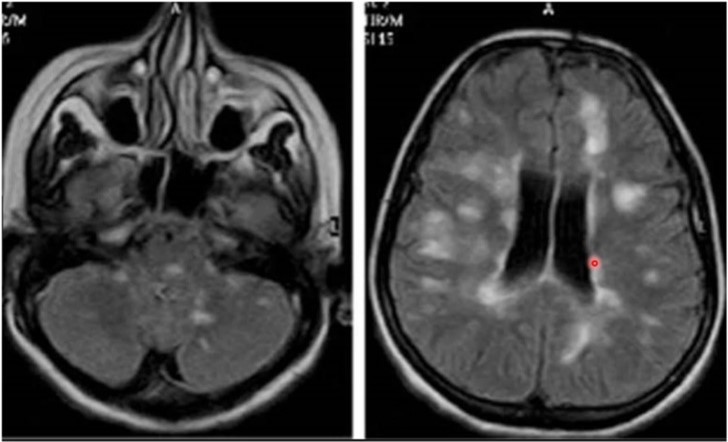

Vad beskrivs?

Central yrsel